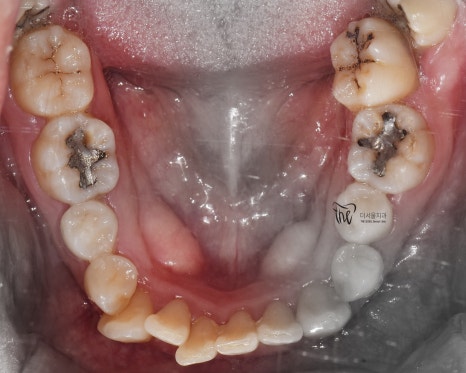

정면에서 봤을 땐, 불규칙한 총생들이 관찰되며

곳곳에 치석이 쌓여있는 것을 볼 수 있습니다.

교합면에서 봤을 땐, 교정치료를 떠나서

선행해야 될 치료들이 많다는 것을 알 수 있습니다.

아말감이 수복 되어있던 곳의, 아말감 탈락에

따른 치질이 드러나 있다던지, 교합면의

다발성 우식증에 따라서 충치치료도 같이

병행을 해야 되는 상황입니다.

가지런한 치열을 얻음에 따라서 구강 위생관리가

조금 더 용이해진 부분.

나아가, 부정교합 2급 이 같이 치료가 되면서

더불어 구강 내 충치들도 깔끔하게 다 제거를

해드리게 되었네요.